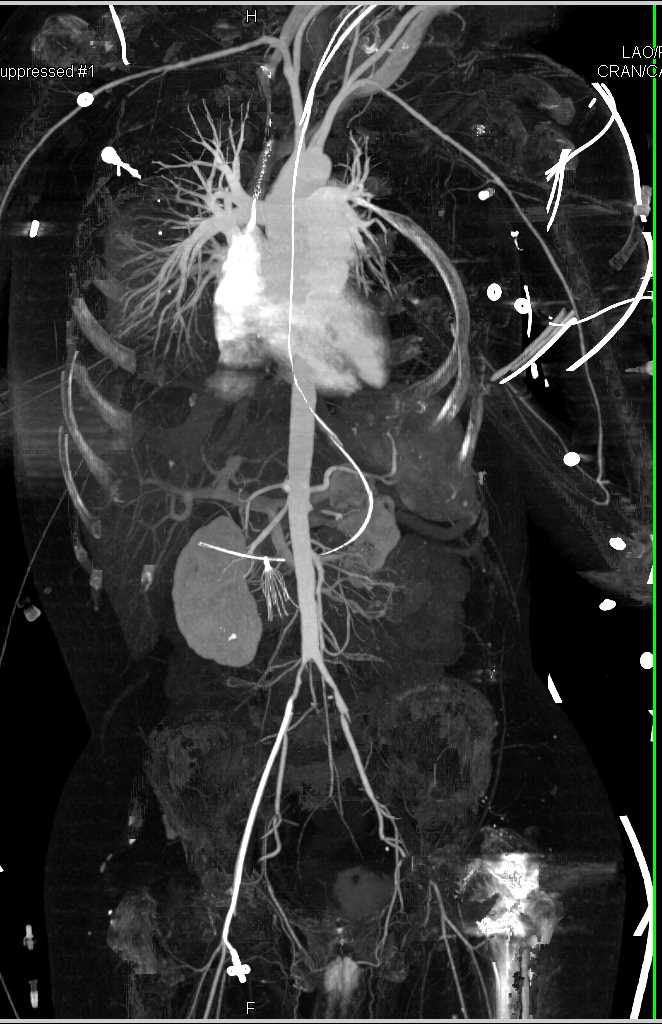

CTA with Occluded Left Superficial Femoral Artery (SFA)